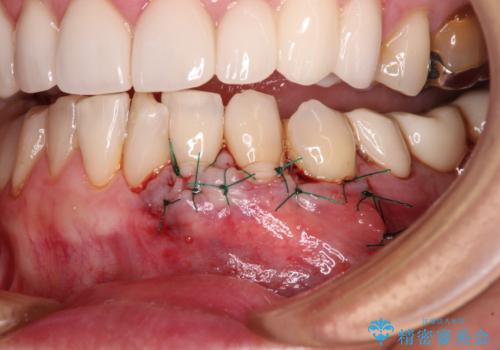

セラミッククラウンによる治療も検討されていましたが、歯肉が非常に薄く、クラウンを装着しても将来的に歯肉退縮を起こす可能性が考えられたので、まずは歯肉移植による根面被覆を行うこととしました。

外科処置に恐怖心があるとのことで、移植手術を行う際には、静脈内鎮静法にてリラックスした状態で処置を受けていただきました(別途税別5万円)。